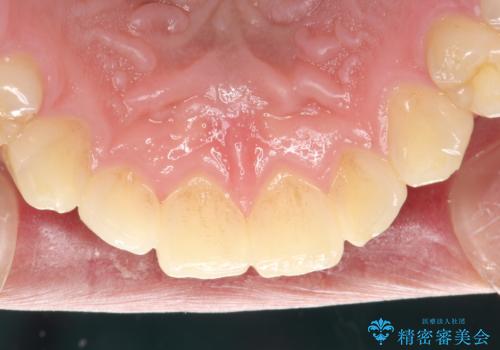

- 半年ぶりの来院で、全体的なチェックとクリーニング希望でした。PMTC(自費クリーニング)60分コースを行いました。

PMTCとは、プロフェッショナル(歯科衛生士)メカニカル(機械的)トゥース(歯)クリーニング(清掃)の略です。歯科医院にて、いろいろな機械・材料を使用し汚れを落とします。

磨き残しや、細菌は歯の表面がザラザラしている部分につきやすいです。そのためPMTCを定期的に繰り返すことで、歯の表面がツルツルの状態である期間が長くなるため、虫歯や歯周病予防につながります。